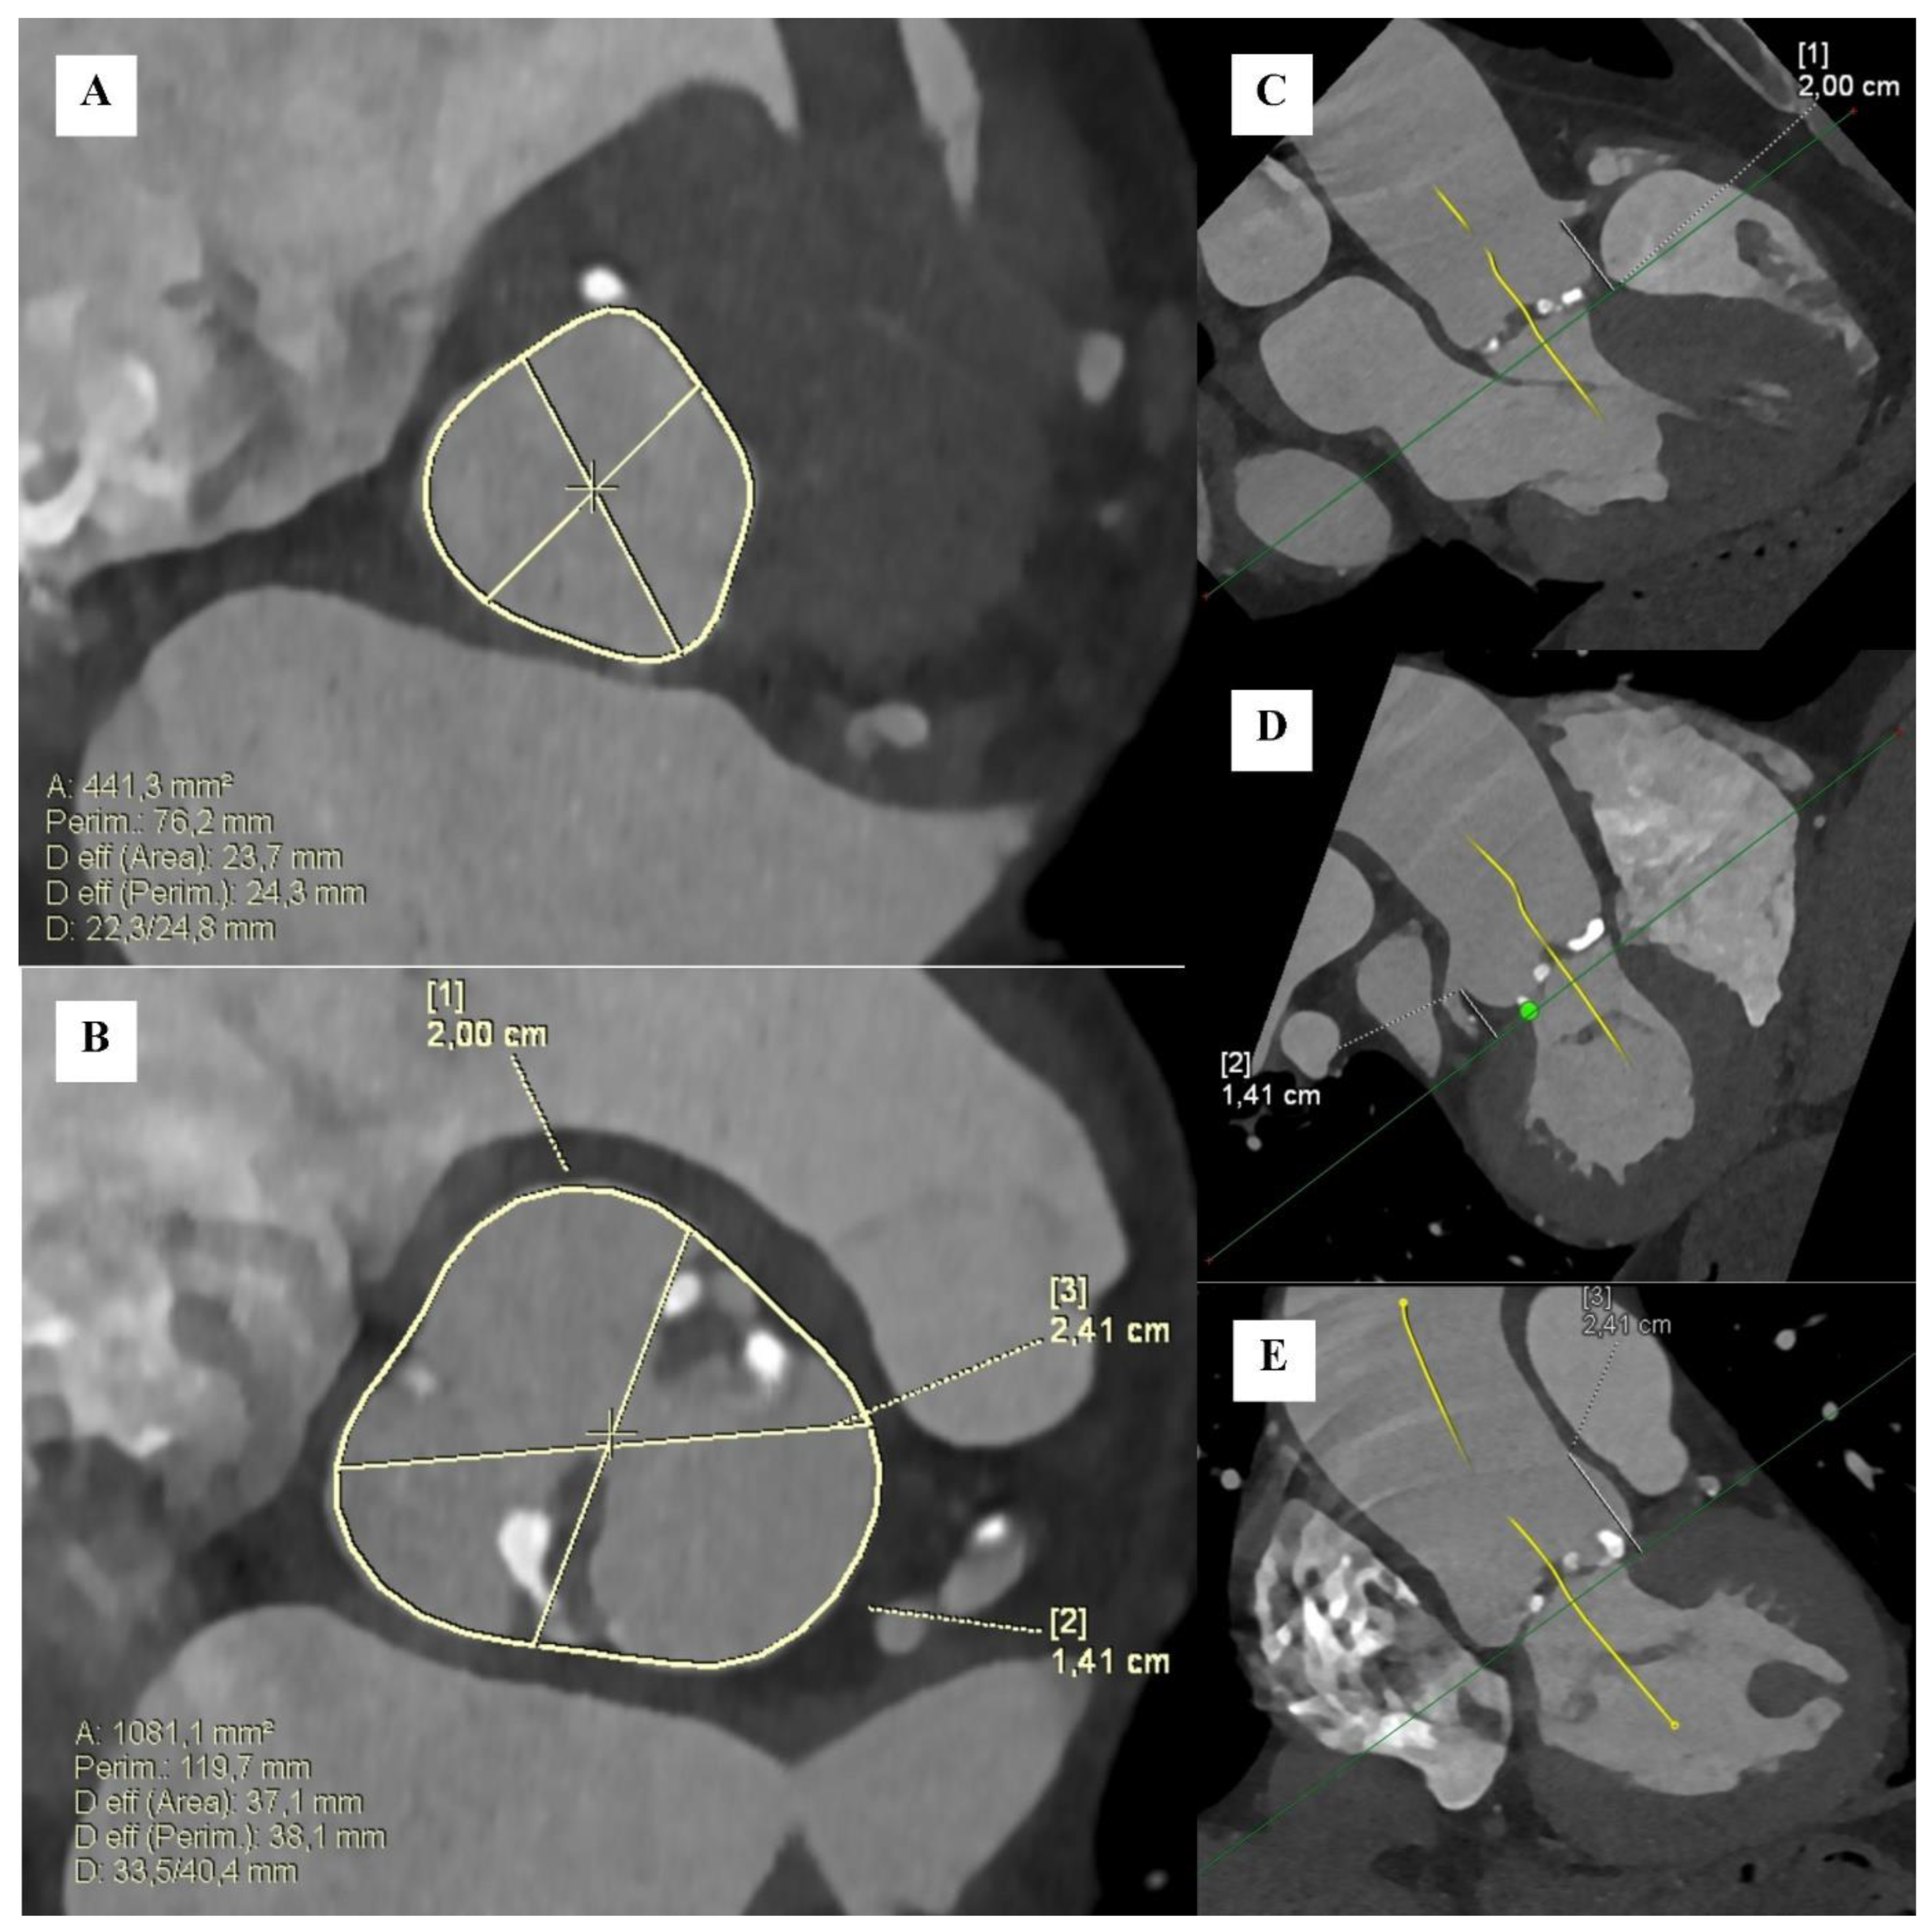

- Kim, W.K.; Renker, M.; Rolf, A.; Liebetrau, C.; Van Linden, A.; Arsalan, M.; Doss, M.; Rieck, J.; Opolski, M.P.; Mollmann, H.; et al. Accuracy of device landing zone calcium volume measurement with contrast-enhanced multidetector computed tomography. Int. J. Cardiol. 2018, 263, 171–176. [Google Scholar] [CrossRef]

- El Garhy, M.; Owais, T.; Lauten, P. Aortic valve calcium volume as measured by native versus contrast-enhanced computer tomography and the implications for the diagnosis of severe aortic stenosis in TAVR patients with low-gradient aortic stenosis. Egypt. Heart J. 2022, 74, 71. [Google Scholar] [CrossRef] [PubMed]